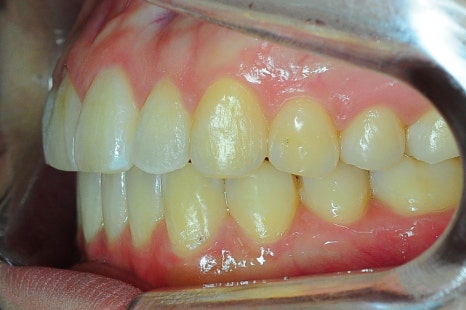

인비절라인 8개월 교정 전후 모습

*치료 기간: 2024.04.21 - 2024.12.22

*치료 전후 사진은 환자의 동의하에 게재하였으며, 동일한 환경과 조건에서 촬영된 전후 사진입니다.